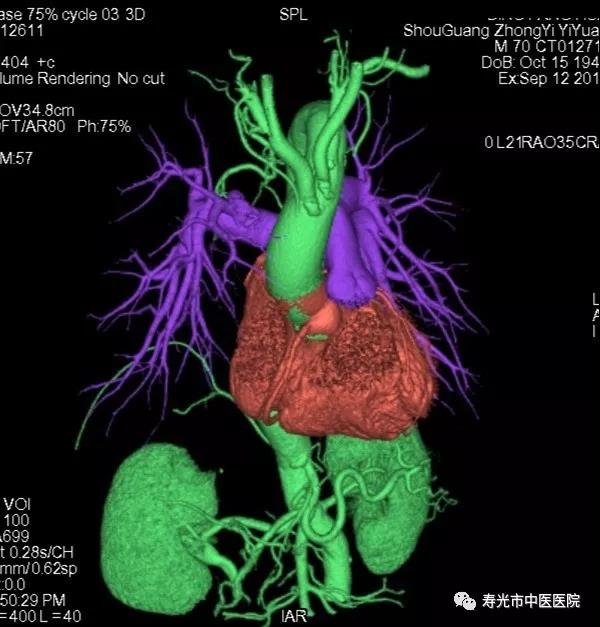

CT检查:清晰成像 挑战重疾

256排Revolution CT被称为“革命型CT”、“CT界的航母”,融合超高端CT的能谱扫描、高时间分辨率扫描和宽体探测器扫描三个领域顶尖科技于一身,实现了无限制1-Beat心脏成像、无限制1-Stop脑卒中成像、多通道主机能谱成像,打造了CT覆盖范围、速度、图像质量、辐射剂量、能谱和扫描舒适性的业界新典范,建立了心血管、神经、肿瘤、呼吸系统、泌尿系统及骨科专业等疾病的成像和低剂量筛查领域全新标准,大幅提高医疗效率和患者体验,有效协助医生进行精准诊断和应对重疾挑战。

如今胸痛病人比较多见,而胸痛确诊需要“排除法”,传统的检查方法是分别做肺动脉、胸主动脉和冠脉的造影,一一排除之后,发现病灶,每次检查都要为患者注射一次对比剂。而使用这台仪器,只需注入一次对比剂,就能完成对这三个部位的检查,实现三联扫。“这给胸痛中心和急性胸痛病症的检查流程改善带来了福音。”

领先之处不仅在此,在做冠脉成像的时候,传统检查需要药物降低患者的心率,使用这台机器,不需要控制心率,只需患者心脏搏动一次,用0.28秒的时间就可以完成。“即使心率不齐的患者,也可以通过这台仪器进行检查。”

CTA成像

CT下冠脉CTA 3D成像